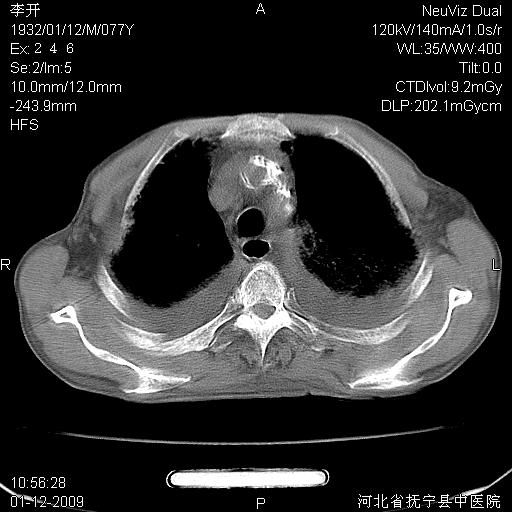

以下是引用黑白光影在2009-1-19 16:49:00的发言:[br]心衰肺水肿;心包、胸腔积液;冠脉钙化;肺部感染。